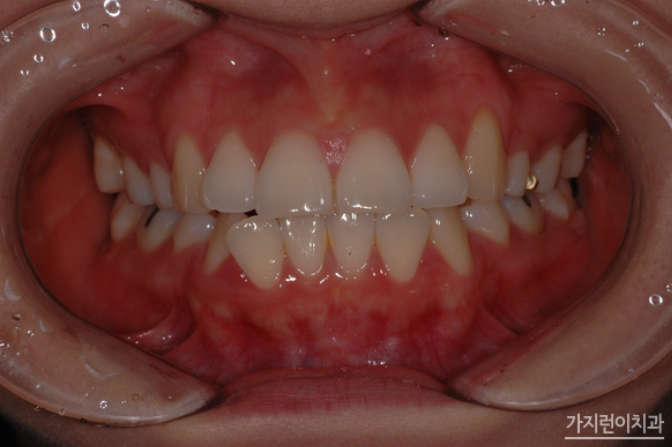

치아교정은 돌출입, 덧니, 주걱턱, 벌어진 치아로 인해 외적인 스트레스를 받는 사람들에게는 심미적인 관점에서 치아교정이 하나의 방법이 될 수 있는데요. 치아교정은 보통 2년이라는 시간이 소요되다 보니 신중에 신중을 기해 시작을 하게 됩니다. 그런데 길다면 길고 짧다면 짧은 2년의 시간 동안 치아교정을 했는데 이런저런 문제로 발생한다면 속상하지 않을 수 없겠죠. 첫 치아교정부터 제대로 교정해서 재교정이 필요하지 않으면 좋겠지만 여러 가지 이유로 재교정이 꼭 필요한 경우라면 어떤 경우가 있을까요?

치아 재교정은 잇몸이나 치아 상태가 약해져 있는 상태에서 다시 시작하는 것이기 때문에, 교정을 전문으로 하는 치과를 선택하는 것이 중요한데요. 경험과 노하우가 있는 의료 인력이 있는 곳을 찾아 상태에 따른 정확한 상담과 치료 계획을 세우는 것이 필요합니다. 그래서 대부분은 치과가 많이 모여있는 밀집된 지역을 선호하시는데요. 이곳저곳 어슬렁 거리면서 나에게 맞는 교정치과를 찾기란 쉽지 않기 때문에 접근성이 편리한 치과 위주, 후기가 좋은 치과 위주로 알아보곤 하십니다.

아무래도 나이가 들수록 잇몸이 약해질 수밖에 없는데요. 치아의 뿌리를 잡고 있는 뼈가 많이 내려가서 치아를 안전하게 잡아주는 능력이 떨어지다 보니 잇몸의 상태에 따라 재교정 가능 여부와 치료 범위를 결정되게 됩니다. 재교정 후에는 치아가 다시 틀어지지 않도록 유지장치를 잘 착용하고 정기 검진을 통해 치아와 잇몸 건강 관리를 잘 하는 것이 중요하겠죠.